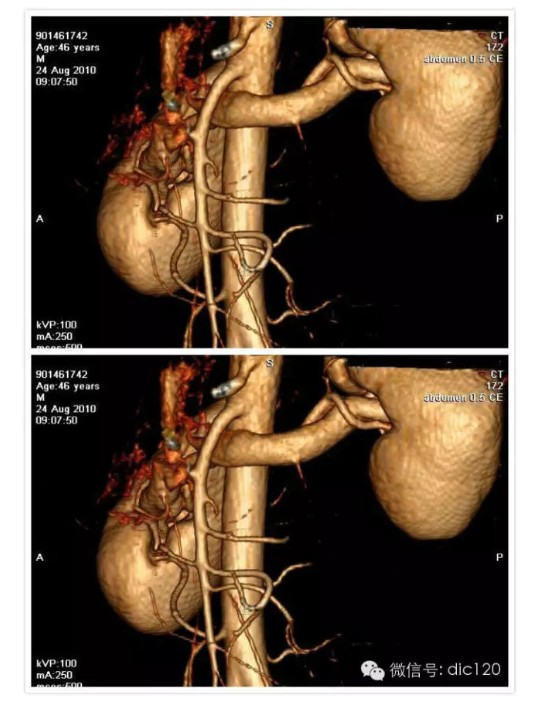

胡桃夹综合征(nutcracker phenomenon)即左肾静脉压迫综合征,又称胡桃夹现象,好发于青春期至40岁左右的男性,儿童发病分布在4~7岁,多发年龄见于13~16岁。 左肾静脉行走在腹主动脉和肠系膜上动脉之间,这两条动脉构成40~60度的夹角,左肾静脉刚好通过此夹角。从解剖上看,右肾静脉径直注入下腔静脉,行程短而直,而左肾静脉需穿过腹主动脉和肠系膜上动脉之间的夹角,跨越腹主动脉前方始能注入下腔静脉,因此左肾静脉远较右肾静脉长。正常时,肠系膜上动脉与腹主动脉之间的夹角被肠系膜、脂肪、淋巴结和腹膜等所充塞,使左肾静脉不致受到压挤。当青春期发育较快、身高迅速增长、脊柱过度伸展、体形急剧变化或肾下垂等情况下,左肾静脉在这个夹角中受到挤压,引起血流变化和相应的临床症状。 胡桃夹现象的主要症状是血尿和蛋白尿,其中无症状肉眼血尿更易发现。血尿的原因是左肾静脉受压致肾静脉高压,左肾静脉扩张所引流的输尿管周围静脉与生殖静脉淤血、与肾集合系统发生异常交通,或部分静脉壁变薄破裂,引起非肾小球性血尿,还会发生睾丸静脉和卵巢静脉淤血而出现肋腹痛,并于立位或行走时加重。另外男性还能发生精索静脉曲张。此外有蛋白尿,不规则月经出血,高血压等。此病的诊断标准为:一侧肾出血;尿红细胞形态为非肾小球性;尿中钙排泄量正常;膀胱镜检查为左侧输尿管口喷血或血性尿;腹部彩超或CT检查可见左肾静脉扩张等。